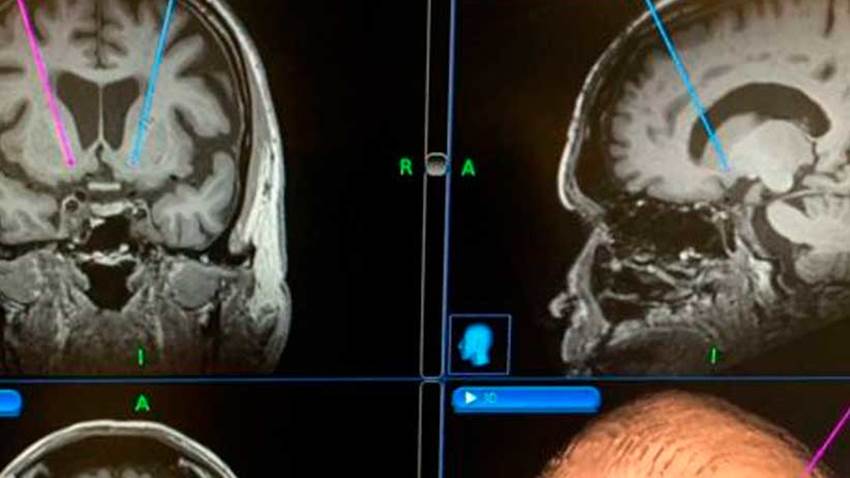

Prueban un implante cerebral para controlar la adicción al alcohol